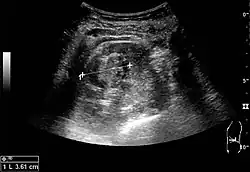

The kidney is divided into parenchyma and renal sinus. The renal sinus is hyperechoic and is composed of calyces, the renal pelvis, fat and the major intrarenal vessels. In the normal kidney, the urinary collecting system in the renal sinus is not visible, but it creates a heteroechoic appearance with the interposed fat and vessels. The parenchyma is more hypoechoic and homogenous and is divided into the outermost cortex and the innermost and slightly less echogenic medullary pyramids. Between the pyramids are the cortical infoldings, called columns of Bertin (Figure 1). In the pediatric patient, it is easier to differentiate the hypoechoic medullar pyramids from the more echogenic peripheral zone of the cortex in the parenchyma rim, as well as the columns of Bertin (Figure 2).[1]

Cortical thickness should be estimated from the base of the pyramid and is generally 7–10 mm. If the pyramids are difficult to differentiate, the parenchymal thickness can be measured instead and should be 15–20 mm (Figure 3). The echogenicity of the cortex decreases with age and is less echogenic than or equal to the liver and spleen at the same depth in individuals older than six months. In neonates and children up to six months of age, the cortex is more echogenic than the liver and spleen when compared at the same depth.[1]

Figure 2. Normal pediatric kidney. * Column of Bertin; ** pyramid; *** cortex; **** sinus.[1] -

Figure 3. Measures of the kidney. L = length. P = parenchymal thickness. C = cortical thickness.[1]